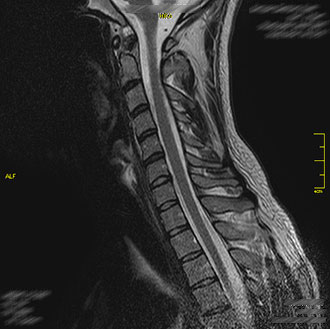

Im Kernspin Zentrum Köln werden alle Abschnitte der Wirbelsäule – Hals-, Brust-, Lenden- sowie Kreuzbeinregion – mit modernster Magnetresonanztomographie untersucht.

Die MRT bietet eine strahlungsfreie und hochauflösende Darstellung von Bandscheiben, Wirbelkörpern, Nerven und dem Rückenmark.

Die MRT der Halswirbelsäule wird häufig bei Nacken- und Armschmerzen, Schwindel, neurologischen Ausfällen oder nach Verletzungen durchgeführt.

Sie erlaubt eine exakte Beurteilung von Fehlstellungen, Bandscheibenvorfällen, Entzündungen, Tumoren, Missbildungen oder einer Nervenwurzelkompression.

Auch Rückenmarksentzündungen (Myelitis) können sicher erkannt werden. Die Untersuchung ist besonders wichtig, um Ursachen für Gefühlsstörungen, Kribbeln oder Lähmungen im Schulter-Arm-Bereich zu identifizieren.